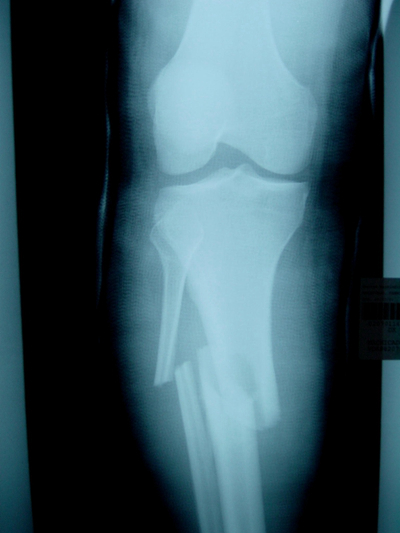

骨折圖片

骨裂